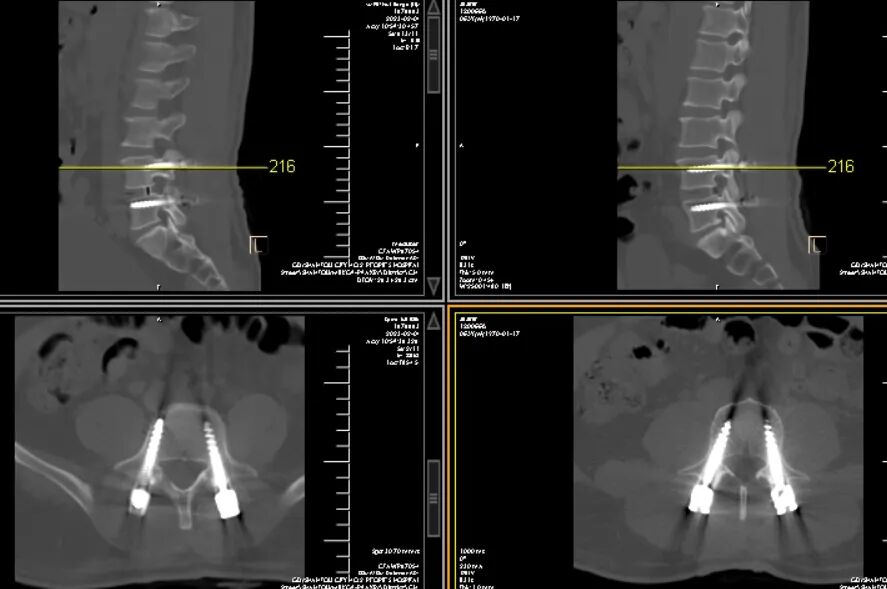

术后CT